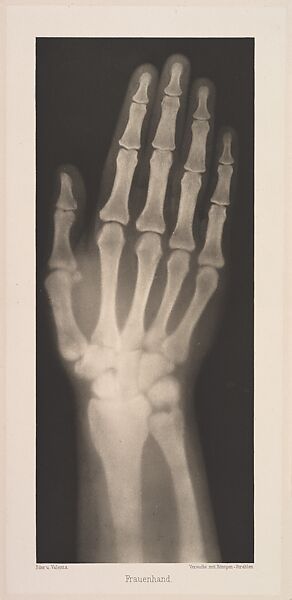

Frauenhand

Eder was the director of an institute for graphic processes and the author of an early history of photography. With the photochemist Valenta, he produced a portfolio in January 1896, less than a month after Wilhelm Conrad Röntgen published his discovery of X-rays. Eder and Valenta’s volume, from which this plate derives, demonstrated the X-ray’s magical ability to reveal the hidden structure of living things. Human hands and feet, fish, frogs, a snake, a chameleon, a lizard, a rat, and a newborn rabbit are all presented in exquisitely printed photo-gravures, as are carved cameos and an assortment of natural materials. In an era when photography’s ability to accurately depict the visible world had become commonplace, this newfound capacity to record the invisible opened up a host of possibilities, both scientific and aesthetic. The careful compositions and shocking appearance of these “Experiments in Photography” link them to the previous century’s tradition of natural-history illustration and point toward the experiments of New Vision photographers in the 1910s and 1920s.

Josef Maria Eder (Austrian, Krems an der Donau, 1855–1944 Kitzbühel) and

Eduard Valenta (Austrian, 1857–1937)

1896

Photogravure

Image: 10 3/16 × 4 1/4 in. (25.9 × 10.8 cm)

Plate: 11 7/16 × 5 5/16 in. (29 × 13.5 cm)

Sheet: 19 5/16 in. × 14 in. (49 × 35.5 cm)